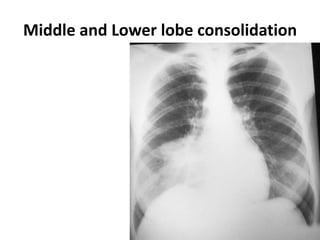

Middle and Lower lobe consolidation

Middle and Lowerlobe consolidation